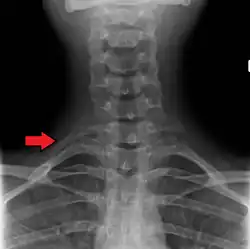

Variations in the number of ribs occur. About 1 in 200–500 people have an additional cervical rib, and there is a female predominance.[13] Intrathoracic supernumerary ribs are extremely rare.[14] The rib remnant of the 7th cervical vertebra on one or both sides is occasionally replaced by a free extra rib called a cervical rib, which can mechanically interfere with the nerves (brachial plexus) going to the arm.